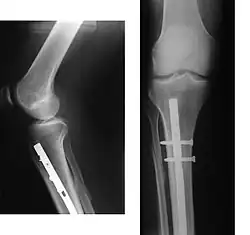

Verriegelungsnagel bei Unterschenkelfraktur

Besonders geeignet für die Versorgung von Schaftbrüchen (z. B. Ober- und Unterschenkel) sind Mark- oder Verriegelungsnägel. Diese werden minimalinvasiv, d. h. nur über kleine Schnitte, entlang der Achse des Knochens in die Knochenhöhle (Markraum) eingebracht und durch quere Schrauben auf beiden Seiten der Fraktur verriegelt. Die Vorteile der Marknagelosteosynthese liegen vor allem in der gewebeschonenden Operationstechnik ohne große Zugänge, der meist geschlossenen Reposition ohne Darstellung des Bruches und der in den meisten Fällen primär belastungsstabilen Fixation. Eine frühfunktionelle Nachbehandlung unter Vollbelastung ist abhängig von der Schwere des Knochenbruchs oft möglich.